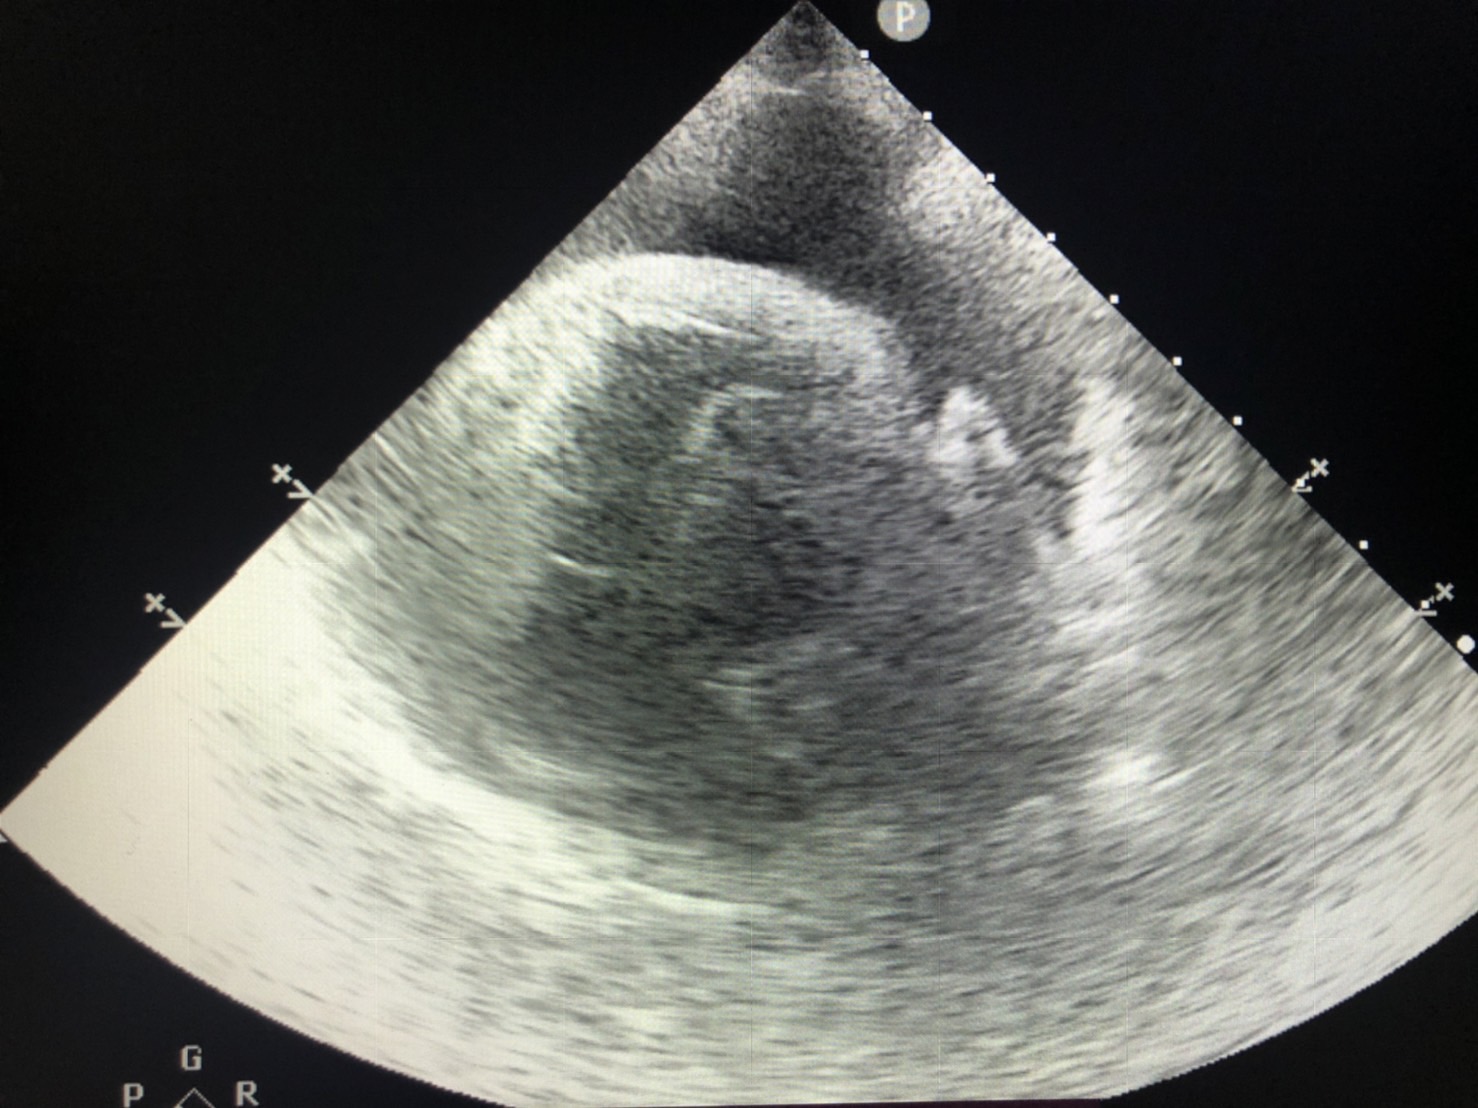

心臟的最外層有一層膜樣構造稱為心包膜,

心臟與膜之間會有少量組織液蓄積其中,達到潤滑的作用。

若是因為腫瘤、心臟疾病、發炎或其他狀況導致液體蓄積在心臟跟心包膜之間,

稱之為心包囊積液。

若是已造成心包填塞的情況下,需抽取心包囊積液,緩解心臟因受到壓迫而造成的致命問題。

同時間需進行身體其他檢查如血液學檢查、X光、心臟超音波等……找到產生心包囊積液的原因。